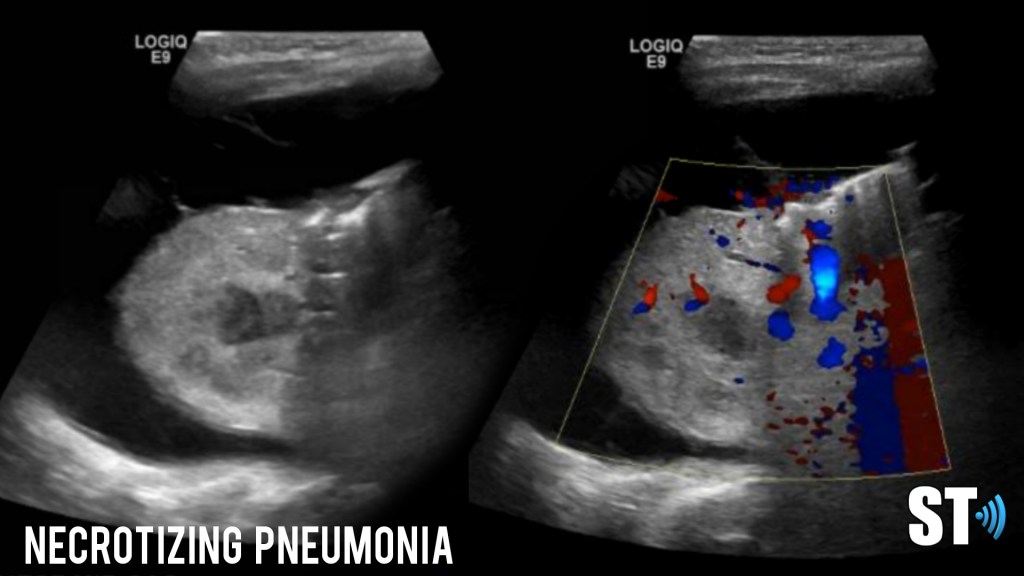

Heterogenous lung with pleural effusion in a patient with necrotizing pneumonia

Necrotizing pneumonia